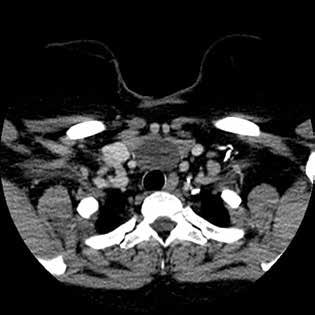

Parathyroid glands undergo a variable descent during embryologic development and can be found anywhere in the neck from the level of the mandible to the mediastinum. To the best of our knowledge, we present the first report of a patient who was found to have bilateral parathyroid adenomas in her pyriform sinuses. A middle-aged woman with renal failure and secondary hyperparathyroidism presented with dysphagia and was found to have bilateral....

A B

Figure 1. A: Axial CT with contrast of the neck and chest demonstrates a homogeneous cystic lesion overlying the inferior border of the thyroid gland, anterior border of the trachea, and the great mediastinal vessels. B: Coronal CT of the cyst demonstrates its cervical and mediastinal components with splaying of the innominate veins.